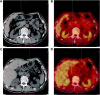

Objective: The current study was designed to analyze the value of 18F-FDG positron emission tomography/computed tomography (PET/CT) combined with carbohydrate antigen 19-9 (CA19-9) in differentiating pancreatic carcinoma (PC) from chronic mass-forming pancreatitis (CMFP) in Chinese elderly.

Methods: As it is impossible to differentially diagnose PC from CMFP, 60 participants older than 65 years with focal pancreatic lesions were scanned by 18F-FDG PET/CT and their CA19-9 levels were tested. Diagnoses of all participants were confirmed by comprehensive methods including aspiration biopsy, surgical pathology, and clinical follow-up of 12 months. Twenty participants with CMFP were included in CMFP group and 40 participants with PC in PC group.

Results: In CMFP and PC groups, 46 participants showed increased 18F-FDG uptake, 43 had elevated CA19-9 levels, and 38 participants had both increased 18F-FDG uptake and elevated CA19-9 levels. Standardized uptake value maximum of PC group (5.98±2.27) was significantly different from CMFP group (2.58±1.81, P<0.05). Sensitivity, specificity, and accuracy of 18F-FDG PET/CT in differentiating PC from CMFP were 95%, 60%, and 83.3%, respectively. CA19-9 levels of PC group (917.44±1,088.24) were significantly different from CMFP group (19.09±19.54, P<0.05). Sensitivity, specificity, and accuracy of CA19-9 levels in differentiating PC from CMFP were 87.5%, 60%, and 78.3%, respectively. Sensitivity, specificity, and accuracy of 18F-FDG PET/CT combined with CA19-9 levels in differentiating PC from CMFP were 90%, 90%, and 90%, respectively.

Conclusion: 18F-FDG PET/CT had reliable sensitivity, specificity, and accuracy in differentiating PC from CMFP, and CA19-9 levels could be helpful in 18F-FDG PET/CT for differentiating PC from CMFP in Chinese elderly. Moreover, 18F-FDG PET/CT combined with CA19-9 levels was found to be an effective method to differentially diagnose PC from CMFP and has paved the way for the timely and safe treatment of PC and CMFP in Chinese elderly.